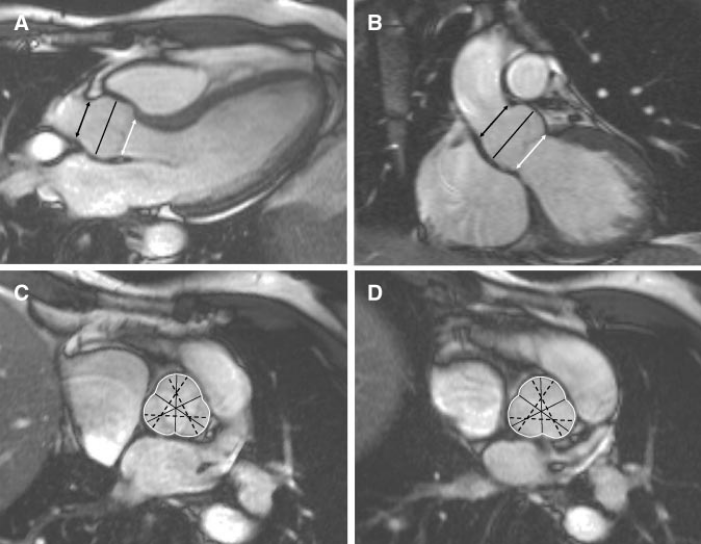

In the LVOT view, the aortic (AO) diameters at the level of aortic valve annulus, the widest point of the AO sinuses, and the sinotubular junction are measured (Davis et al., 2014).

The levels of annulus, sinus, and sinotubular junction measurements (white arrow, black line, and black arrow, respectively).